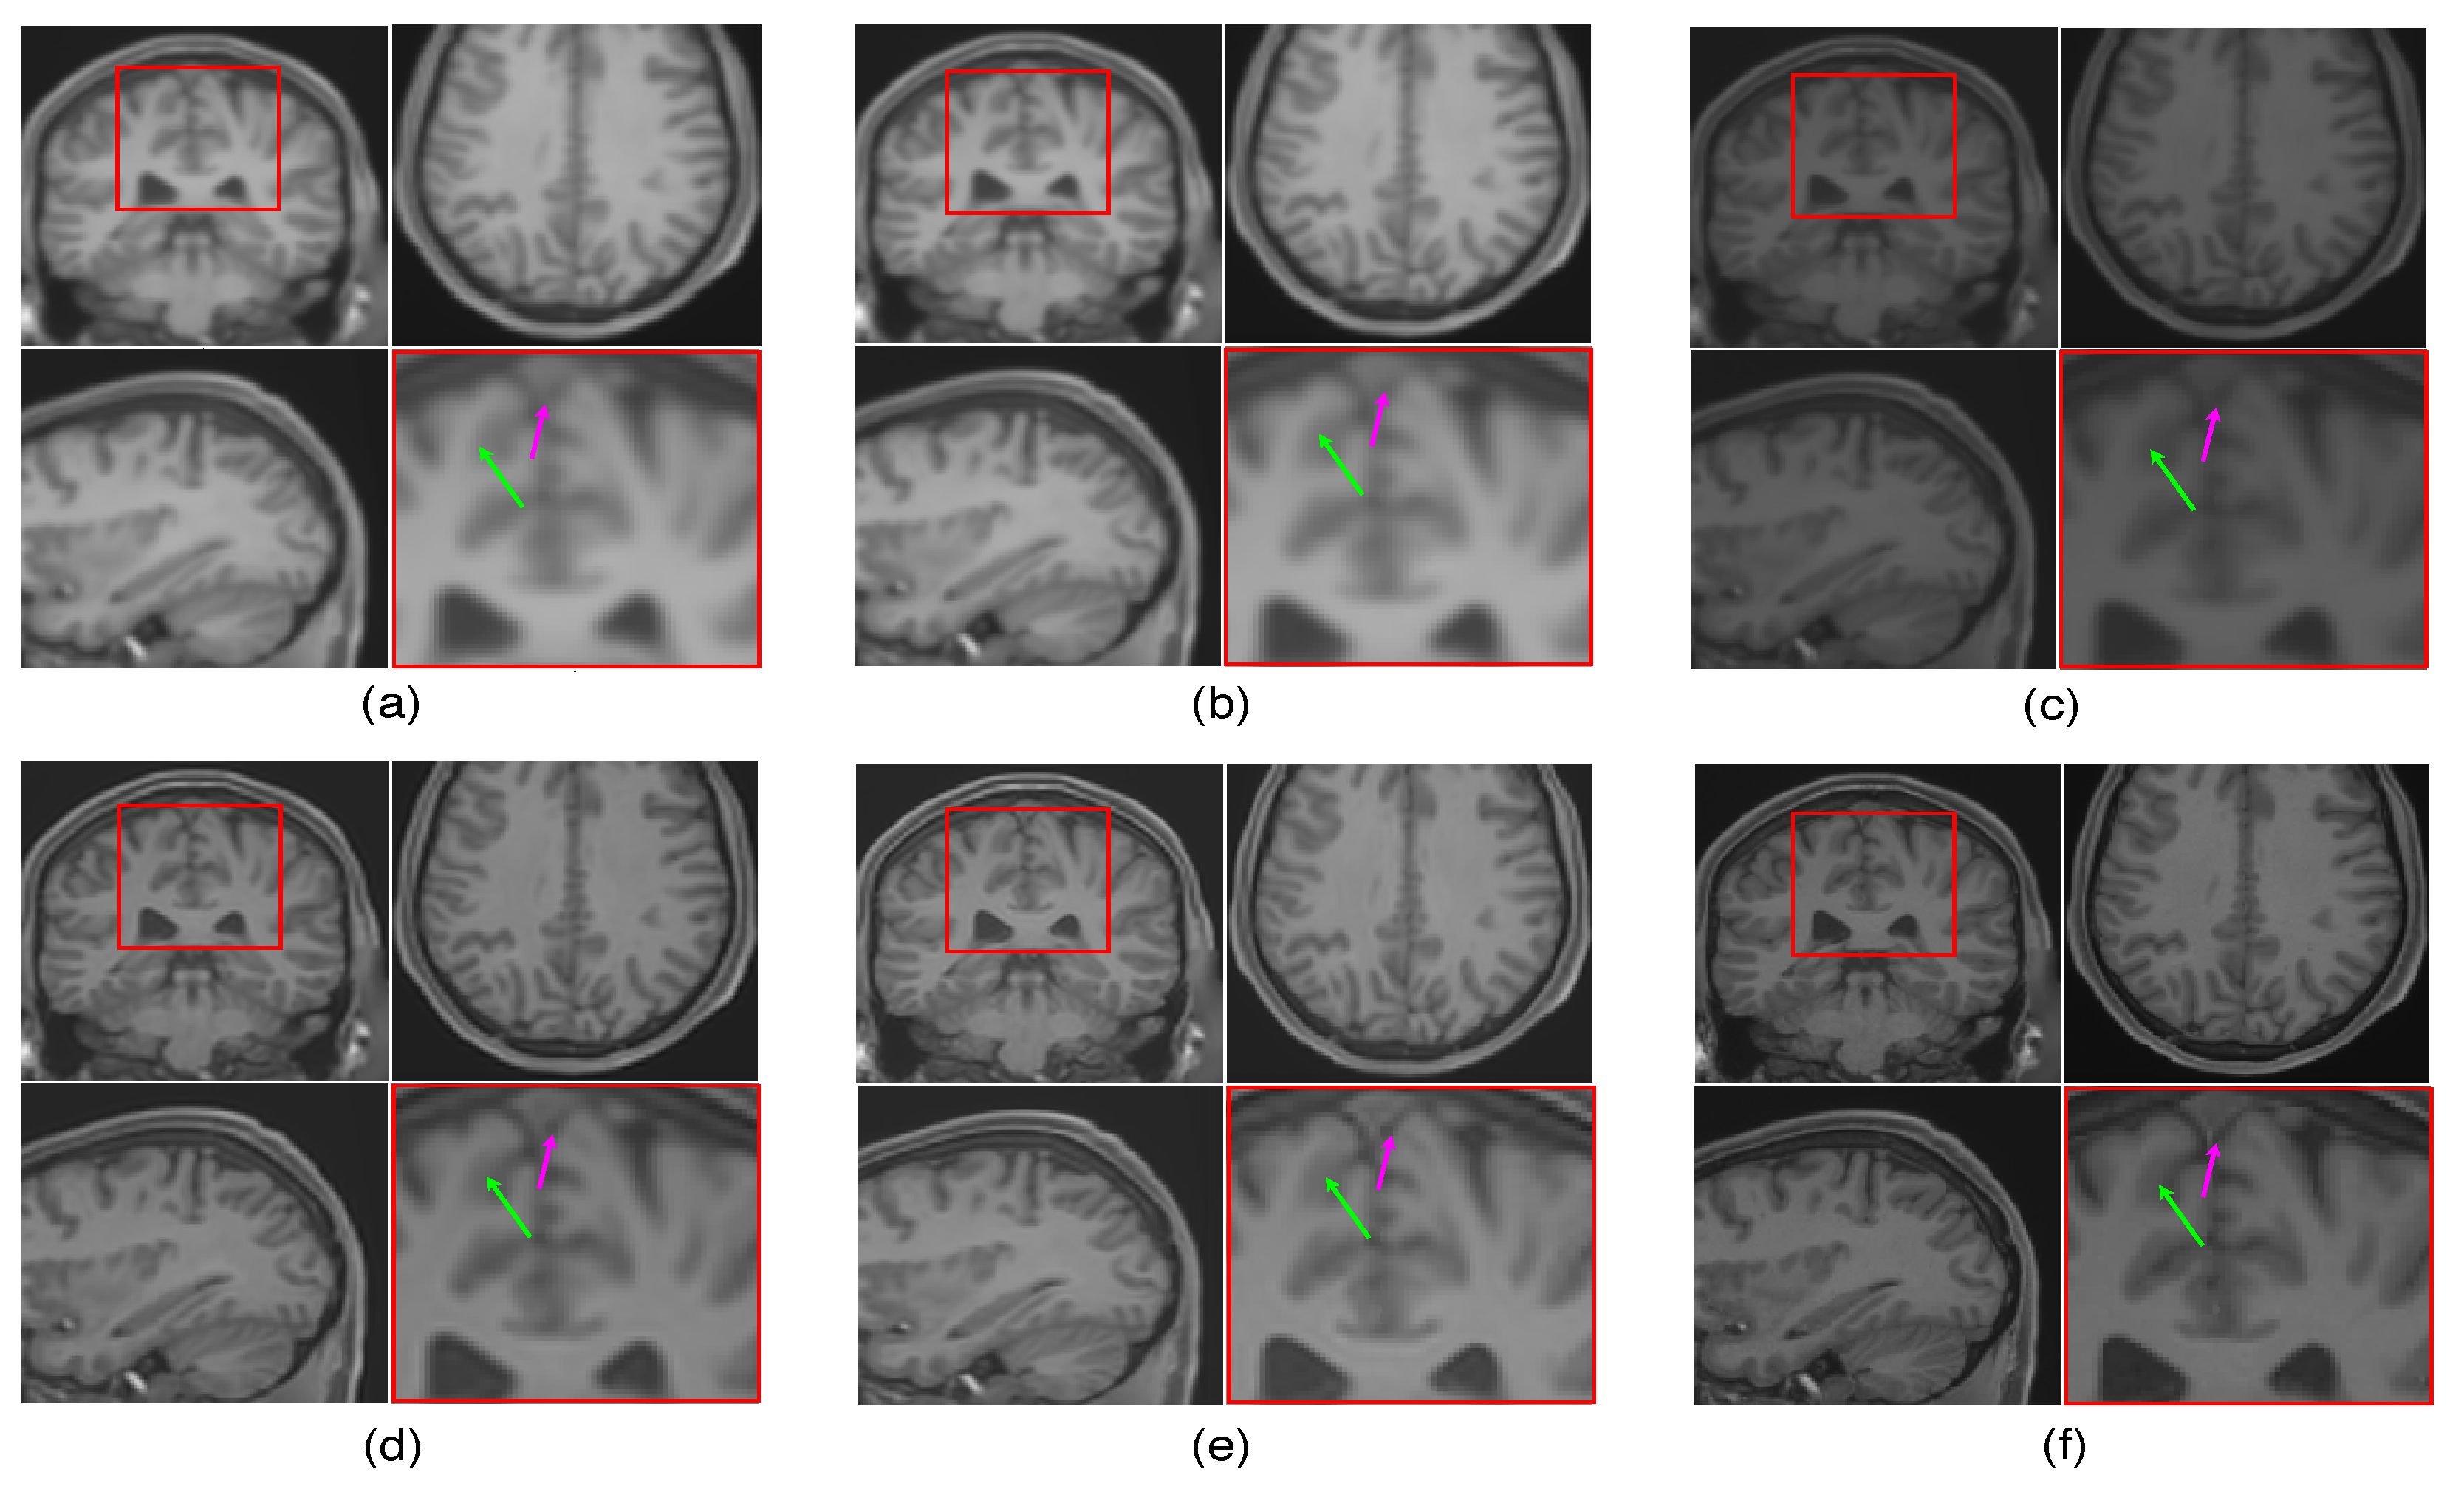

The LR image volumes are simulated by blurring the HR image volumes using a Gaussian kernel of the standard deviation of one voxel size and followed by downsampling. One MR image volume is randomly selected from dataset-II and super-resolved with super-resolution factor (SRF) 2 using the proposed SR approach and is compared with the existing state-of-the-art unsupervised methods NLM3D [13] and LRTV [12]. The reconstructed images using these approaches are shown in Figure 9. The highlighted region in the coronal slice is zoomed and shown in the red box. The pink and green arrows show the location for tissue boundary between cerebrospinal fluid (CSF) and gray matter, and white matter and gray matter, respectively. It can be observed that the proposed approach reconstructs the image details with relatively sharper tissue boundaries as well as better preservation of image details (near green arrow) as compared to the existing methods. Table 2 shows the mean PSNR, SSIM and FSIM values computed for different subjects for SRFs 2 and 3 reconstructed by different methods. The graphical representation of Table 2 is shown in Figure 10. It can be observed that the proposed approach provides comparably higher PSNR, SSIM, and FSIM values than existing methods, and thus illustrates the advantages of the proposed work in pixel-intensity, and structural and gradient-feature-based similarities, respectively.

Figure 9.

Illustration of reconstruction results for real MR image volume for super-resolution factor 2 using different super-resolution algorithms: (a) nearest neighbor interpolation, (b) spline interpolation, (c) non-local means [13], (d) low rank and total variation (LRTV) [12], (e) the proposed method, and (f) the original denoised high resolution (HR) image. Zoomed version of the red box shown in the axial slice is shown to demonstrate the difference (specifically in tissue boundaries indicated with arrows).